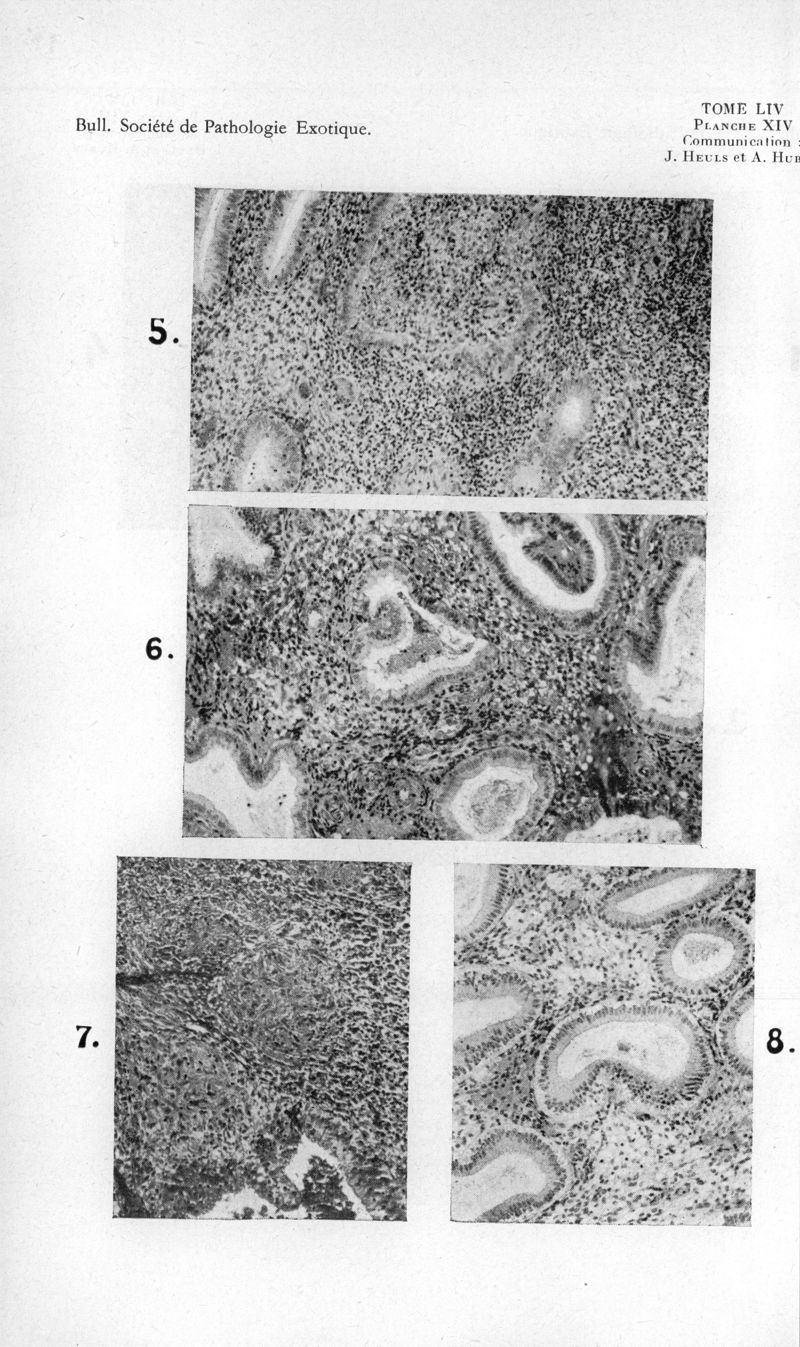

Bulletin de la Société de pathologie exotique et de ses filiales

1961, tome 54. - Paris : Masson, 1961.